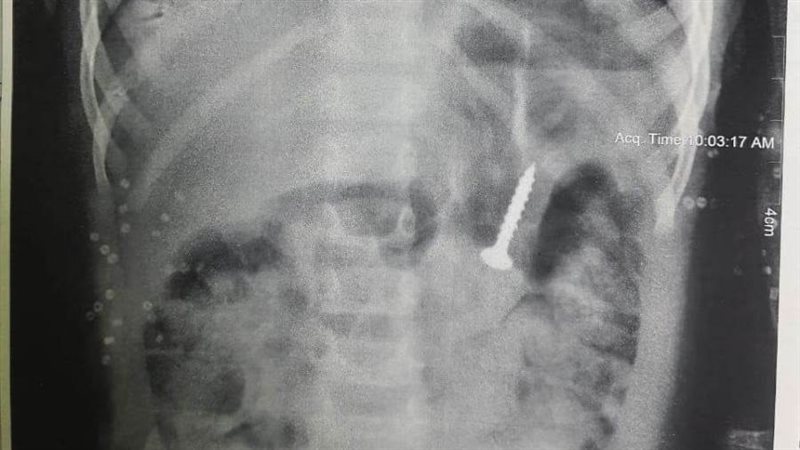

استخراج "مسمار" من معدة طفلة بمستشفى المنصورة التخصصي

تمكن فريق طبي بمستشفى المنصورة التخصصي، من استخراج "مسمار" من معدة طفلة رضيعة، بعدما ابتلعته عن طريق الخطا، وذلك دون تدخل جراحي.

وقال المستشفى في بيان صادر عنه، إن وحدة الجهاز الهضمي ومناظير الأطفال استقبلت طفلة تبلغ من العمر عامين، مصابة بحالة إعياء، وبعد عمل أشعة على المعدة تبين وجود جسم غريب "مسمار".

وأضاف البيان، أن الطفلة ابتلعت الجسم بالخطأ، وجرى استخراجه باستخدام تقنية المنظار دون تدخل جراحي، ووضع الحالة تحت الملاحظة.